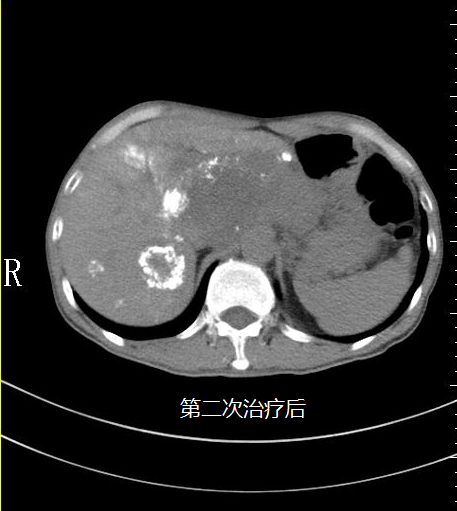

蘇先生進行第二次微血管介入治療后明顯感受自己的身體變得輕盈,可以進行簡單的飲食,精神狀態(tài)變好了。

在5月3日蘇先生的肝指標檢查中甲胎蛋白降為6671IU/ml(參考值0~5.8),隨后王峰醫(yī)生實時跟進蘇先生病情為他制定后續(xù)的治療方案,為他開對應的藥物治療;5月14日蘇先生的肝指標檢查中甲胎蛋白降為18.70U/ml(參考值0~5.8)。

5月18日是蘇先生進行第三次微血管介入治療,治療后蘇先生完全可以自理,飲食恢復正常,面色也慢慢紅潤起來,腫瘤從原來的16公分縮小至10公分,甲胎蛋白逐漸趨向正常,看到這樣的結果也讓醫(yī)生們深感很欣慰,連蘇先生也意想不到,前段時間自己還是生命瀕危的癌癥患者現(xiàn)在卻可以像正常人一樣生活。他覺得這是上天給他最大的驚喜。